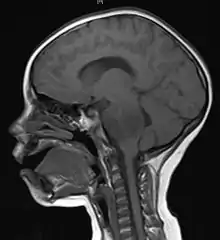

A brainstem glioma in four-year-old. MRI, sagittal, without contrast

Led by Prof. Nori Kasahara, researchers from USC, who are now at UCLA, reported in 2001 the first successful example of applying the use of retroviral replicating vectors towards transducing cell lines derived from solid tumors.[112] Building on this initial work, the researchers applied the technology to in vivo models of cancer and in 2005 reported a long-term survival benefit in an experimental brain tumor animal model.[113] Subsequently, in preparation for human clinical trials, this technology was further developed by Tocagen (a pharmaceutical company primarily focused on brain cancer treatments) as a combination treatment (Toca 511 & Toca FC). This has been under investigation since 2010 in a Phase I/II clinical trial for the potential treatment of recurrent high-grade glioma including glioblastoma multiforme (GBM) and anaplastic astrocytoma. No results have yet been published.[114]